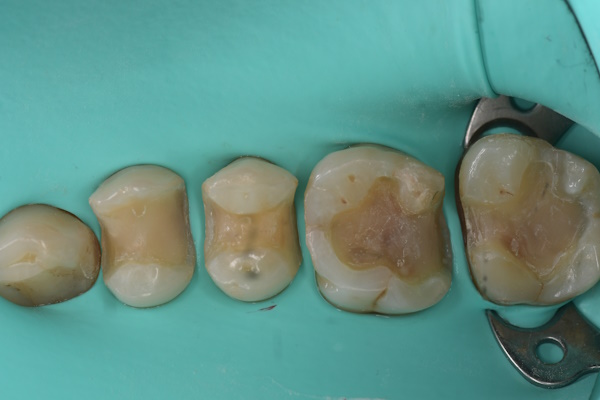

虫歯処置後